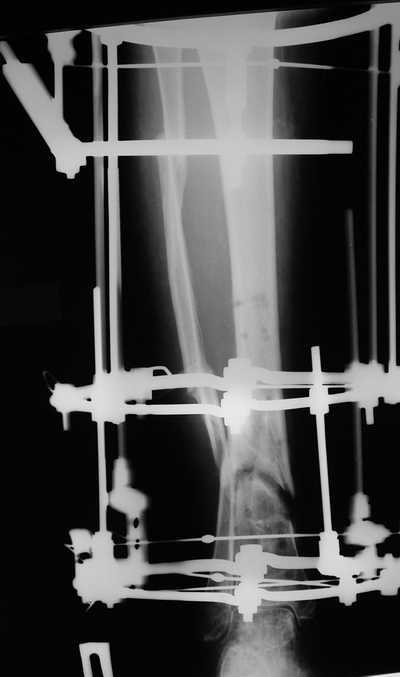

Мужчина, 33 года, резекция б\б кости по поводу остеомиелита после открытого перелома. Стандартная методика билокального остеосинтеза (рис 1 и 2). В конце удлинения выявилось неудовлетворительное взиморасположение перемещенного фрагмента и дистального отломка (рис 3). Планирование (рис 4).

Адаптация отломков гексаподом за 5 дней (рис 5). Замена гексапода на обычные штанги (рис 6 и 7)